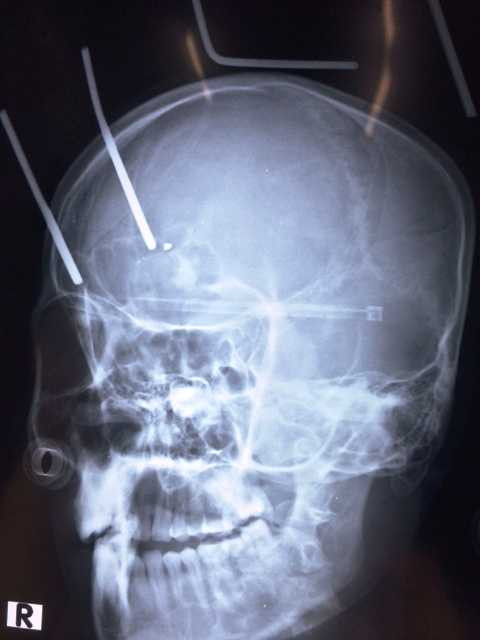

Ảnh chụp 2 chiếc răng cào bằng sắt xuyên vào đầu anh Tú

Trước đó, đêm 22/9, anh Tú nhập viện trong tình trạng bị một chiếc cào răng sắt cắm chặt vào đầu, trong đó 2 chiếc răng cào xuyên từ đỉnh đầu xuống não, sâu gần 9cm. Bệnh nhân mất máu nhiều, bất tỉnh và có nguy cơ tử vong cao.